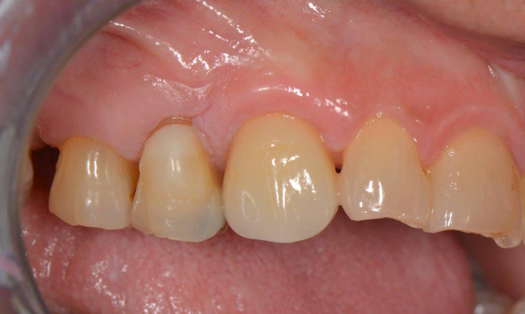

Fig 11. Preoperative healed sites.

Figure 11

Figure 10 through Figure 13 show the preoperative x-ray and the sequence of beginning with healed sites through the surgical placement of the implants. The implants were protected by an Essix-style wound-protection removable retainer for approximately 12 weeks. After the integration phase, the implants and the natural dentition were prepared using traditional crown-and-bridge high-speed diamond and zirconia cutting burs to remove decay and existing restorative materials, to complete and refine the natural-tooth structures to receive full-crown coverage, and to prepare and refine gingival margins of the zirconia implants where needed.